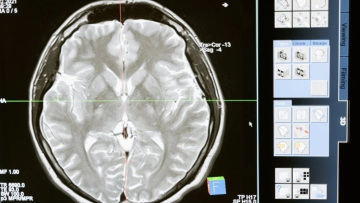

Μια νέα τεχνική που χρησιμοποιεί βαθιά εγκεφαλική διέγερση των κύριων εγκεφαλικών νευρωνικών δικτύων στον θάλαμο ξεπέρασε τις προσδοκίες των ερευνητών στη θεραπεία των γνωστικών διαταραχών έπειτα από τραυματική εγκεφαλική βλάβη, σύμφωνα με δημοσίευση στο περιοδικό «Nature Medicine».

Η βαθιά («εν τω βάθει») εγκεφαλική διέγερση, ή όπως είναι γνωστή διεθνώς με τον όρο DBS (Deep Brain Stimulation) αποτελεί μια συνδυασμένη νευροχειρουργική και νευροφυσιολογική μέθοδο θεραπευτικής διέγερσης για ασθενείς με νευρολογικά νοσήματα.

Στο πλαίσιο της έρευνας, γιατροί εμφύτευσαν χειρουργικά μια συσκευή στον εγκέφαλο πέντε ασθενών με μόνιμες γνωστικές διαταραχές για περισσότερα από δύο χρόνια έπειτα από μέτρια έως σοβαρή τραυματική εγκεφαλική βλάβη. Οι ασθενείς ήταν ηλικίας 22-60 ετών. Η πρόκληση ήταν η τοποθέτηση της συσκευής διέγερσης με ακρίβεια στη σωστή περιοχή, η οποία διέφερε από άτομο σε άτομο. Έτσι, δημιούργησαν ένα εικονικό μοντέλο του κάθε εγκεφάλου που τους επέτρεψε να εντοπίσουν τη θέση και το επίπεδο διέγερσης.

Στη συνέχεια βαθμονόμησαν προσεκτικά την ηλεκτρική δραστηριότητα της συσκευής για να διεγείρουν τα δίκτυα που είχαν επηρεαστεί από τον τραυματισμό. Στο τέλος της θεραπείας, έπειτα από 90 ημέρες, η πειραματική συσκευή βαθιάς εγκεφαλικής διέγερσης αποκατέστησε, σε διαφορετικό βαθμό, τις γνωστικές ικανότητες που οι ασθενείς είχαν χάσει λόγω εγκεφαλικών κακώσεων πριν από χρόνια. Κατά μέσο όρο οι συμμετέχοντες βελτίωσαν την ταχύτητά τους σε ένα τεστ ταχύτητας νοητικής επεξεργασίας (trail-making test) κατά 32%.

Για τους συμμετέχοντες και τις οικογένειές τους οι βελτιώσεις ήταν εμφανείς στην καθημερινή τους ζωή. Επανέλαβαν δραστηριότητες που έμοιαζαν αδύνατες: διάβασαν βιβλία, παρακολούθησαν τηλεοπτικές εκπομπές, έπαιξαν βιντεοπαιχνίδια ή ολοκλήρωσαν μια εργασία για το σπίτι. Αισθάνονταν λιγότερο κουρασμένοι και μπορούσαν να βγάλουν τη μέρα τους χωρίς να κοιμούνται.

Η κλινική δοκιμή προσφέρει ελπίδα σε πολλούς που έχουν σταματήσει να αναρρώνουν. Ο στόχος της ερευνητικής ομάδας είναι να εξελίξει την έρευνα σε θεραπεία. Ωστόσο, όπως σημειώνει απαιτούνται περαιτέρω μελέτες σε μεγαλύτερες κλινικές δοκιμές για να επικυρωθεί η αποτελεσματικότητα της θεραπείας.